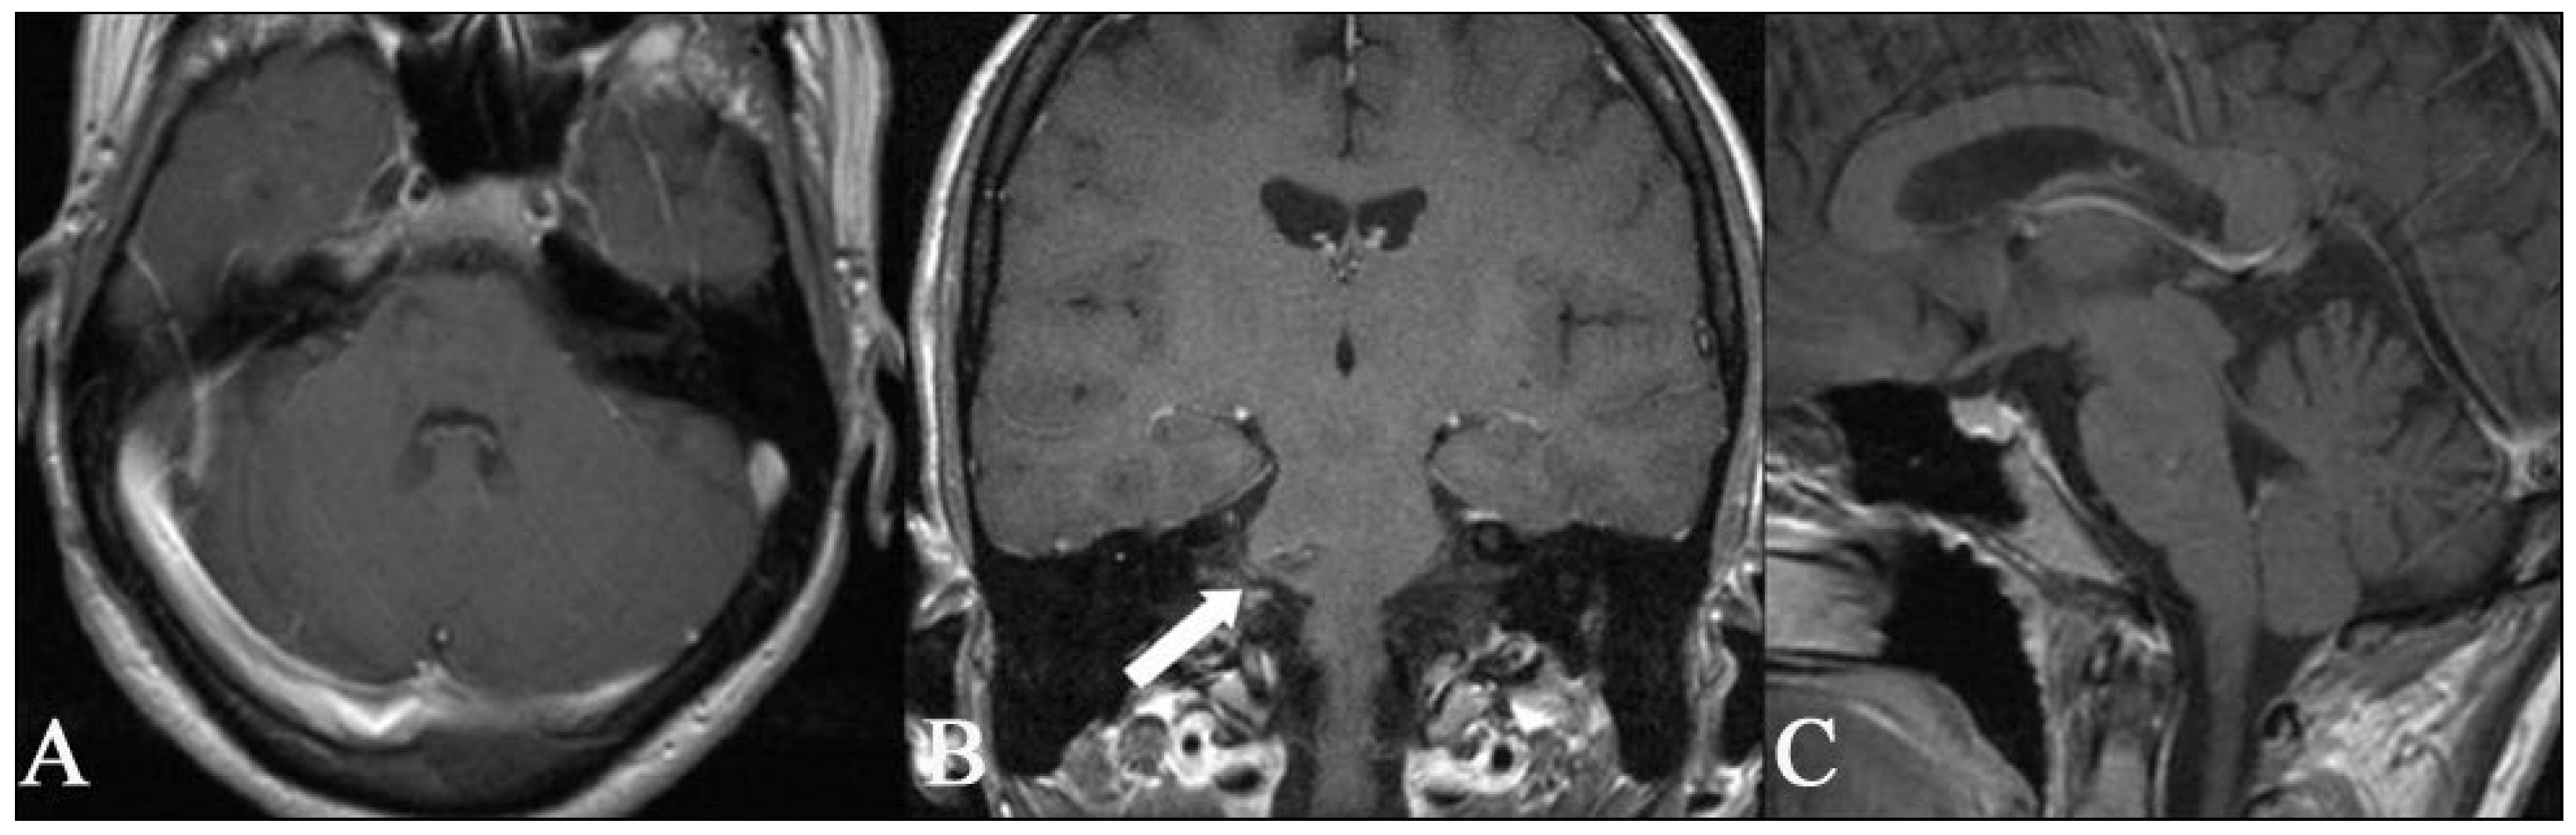

Figure 6. Postoperative axial (A) T1 and coronal T2 images (B) MR show that complete removal of the deep-seated cavernous malformation of the brainstem was achieved. The coronal image on the right shows the entry site into the brainstem (white arrow) through which the cavernoma was accessed. The patient was neurologically stable after surgery. She had no new neurologic deficits after surgery, either in the immediate postoperative period or during the 3-month follow-up.